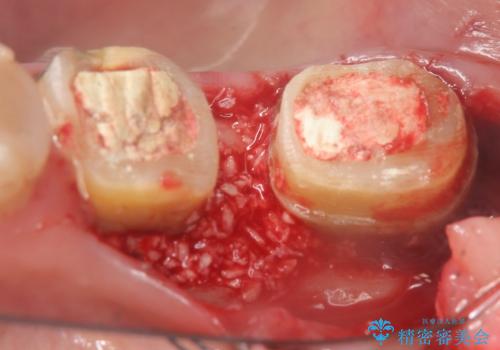

抜歯も検討されるような骨の形態ではありますが、歯周病により溶けてしまった骨を再生させる歯周病再生治療を行うこととしました。

1年間他の治療を行いながら待ったのち、骨の状態確認を行う確定外科の際にしっかりと骨の再生が認められました。